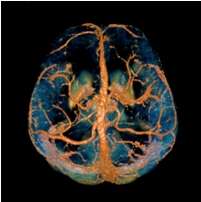

Quantitative Susceptibility Mapping (QSM) provides a novel contrast mechanism in Magnetic Resonance Imaging (MRI) different from traditional Susceptibility Weighted Imaging.[1][2][3][4][5] The voxel intensity in QSM is linearly proportional to the underlying tissue apparent magnetic susceptibility, which is useful for chemical identification and quantification of specific biomarkers including iron, calcium, gadolinium, and super paramagnetic iron oxide (SPIO) nano-particles. QSM utilizes phase images, solves the magnetic field to susceptibility source inverse problem, and generates a three-dimensional susceptibility distribution. Due to its quantitative nature and sensitivity to certain kinds of material, potential QSM applications include standardized quantitative stratification of cerebral microbleeds and neurodegenerative disease, accurate gadolinium quantification in contrast enhanced MRI, and direct monitoring of targeted theranostic drug biodistribution in nanomedicine.